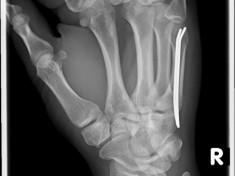

Röntgenbilder